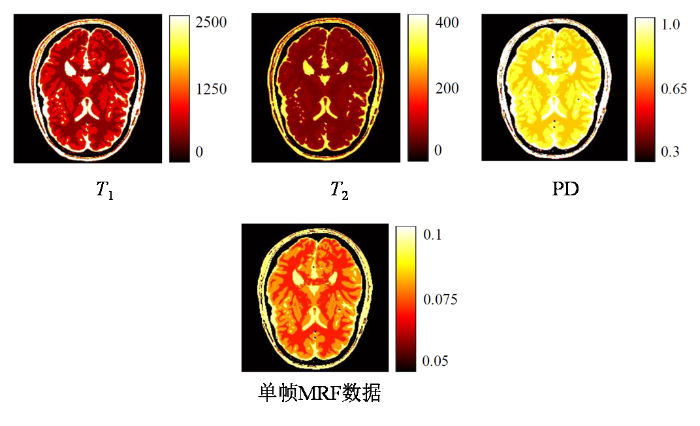

BrainWeb仿真数据 :BrainWeb[26 ] 是由加拿大麦吉尔大学蒙特利尔神经学研究所开发的脑部磁共振仿真数据库.基于该数据库生成的数据集被广泛应用于MRF重建算法的验证.本文利用该数据库提供的健康人脑离散解剖模型(包含20例受试者数据)构建仿真数据集.该模型通过体素级分类标签表征组织构成,具体来说,每个体素被赋予特定整数值(0~11),代表该空间位置的主导组织类型.通过为每个类别赋予文献[27 ] 对应的参数基准值,生成包含T 1 、T 2 与PD三种组织参数的定量参数图数据.随后将其空间分辨率调整至与活体数据一致,并引入体素级随机扰动以模拟组织参数的生理性波动. 最后采用基于布洛赫方程的快速磁共振信号仿真方法——扩展相位图(Extended Phase Graph, EPG)[28 ] ,按照与实采活体数据完全相同的脉冲序列设计及欠采样方案进行数值模拟,并在模拟生成的k 空间添加相同水平的噪声,共生成320组仿真实验数据,划分为训练集(来自18位受试者的288个切片)、验证集(来自1位受试者的16个切片)和测试集(1位受试者的16个切片).图6 展示了其中一组数据的定量参数图与单帧MRF数据.

图6

仿真生成的BrainWeb数据示意图

Fig. 6

Schematic diagram of BrainWeb data generated by simulation